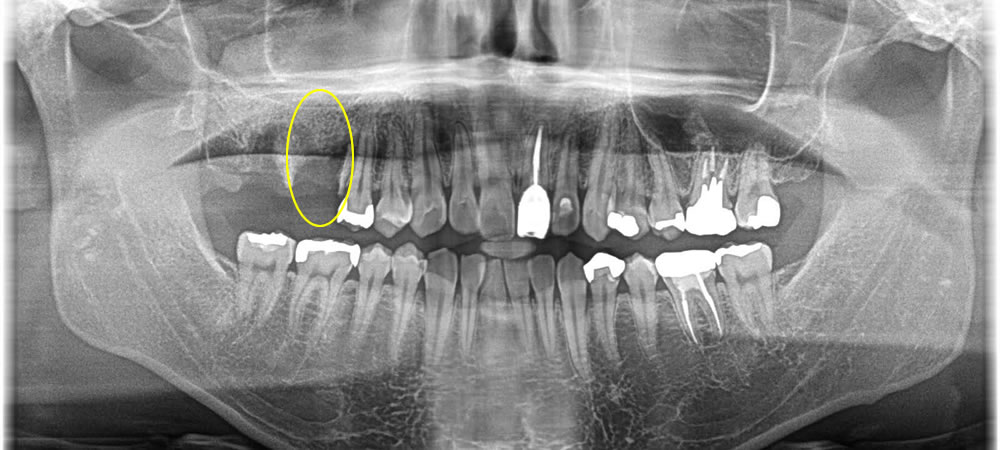

保存不可能な歯を抜歯即時インプラントで治療した症例

年齢

30代

性別

女性

症例を見る